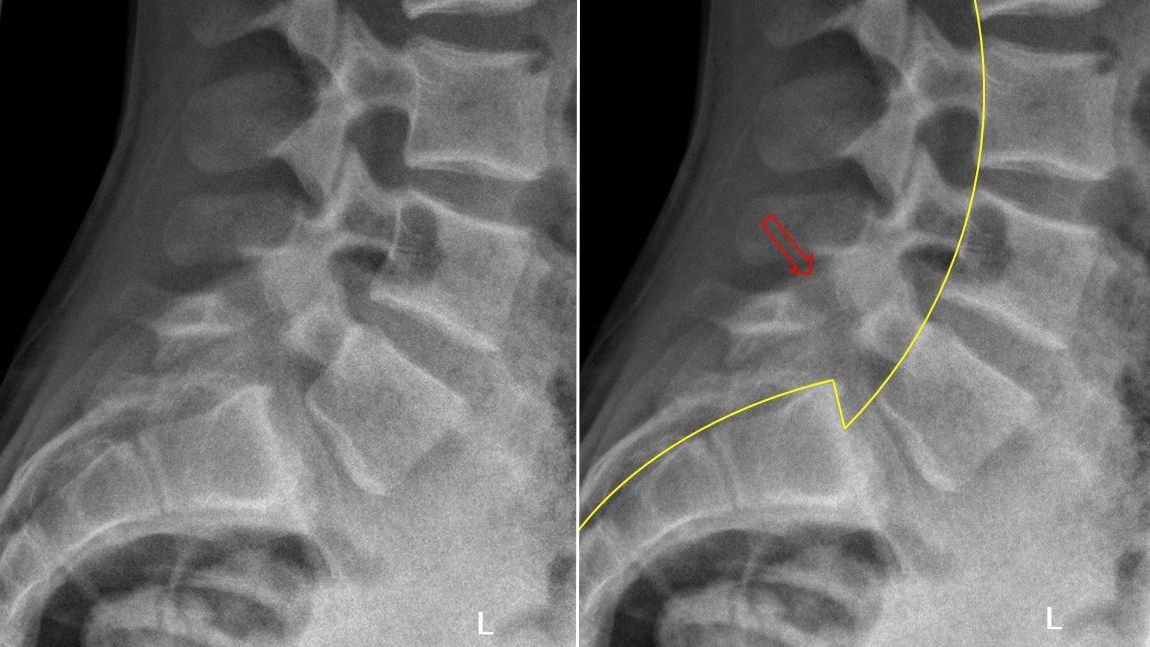

Een spondylolyse is een onderbreking in de wervelboog van een lendenwervel. Deze kan acuut optreden na intense beoefening van bepaalde sporten maar kan ook toevallig vastgesteld worden en dus reeds langer bestaande zijn. Wanneer een spondylolyse zich aan weerszijden van eenzelfde wervelboog voordoet, kan dit (vooral tijdens de groeispurt) tot een afschuiving van het ene wervellichaam ten opzichte van het andere leiden (=spondylolisthesis).

Bij acuut optreden van lage rugpijn en vermoeden van spondylolyse is botscan het ideale onderzoek. Een staande klassieke radiografie kan ons een beeld geven van de werkelijke graad van afschuiven. In liggende positie zien we immers dat de wervel terug op zijn plaats komt te staan. Bij aanwezigheid van beenpijn is verder onderzoek dmv NMR aangewezen.